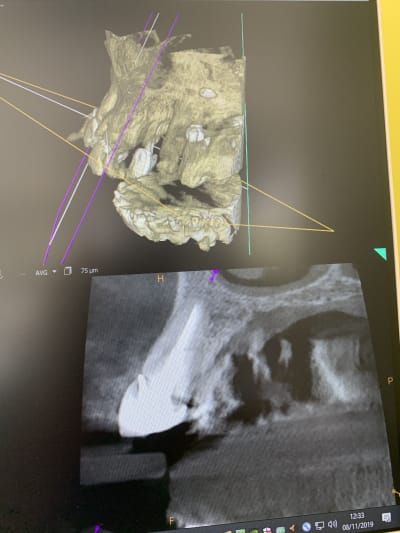

Il y a vraiment des différences de dingue entre les machines !

Les images 3 et 4, les images 6 et 7 sont prises à quelques années d’intervalles.

La machine de 2008 fait très peu d’artefacts, celle de 2018 énormément. Elle à le mar pour les « supprimer », mais ça n’arrange rien !

Les artefacts métalliques sont bien différents selon les machines.

A l’adf on me dit « regardez on voit même les spires des implants », avec ma bécanne de 2008 je vois les spires des vis dans les implants, les têtes de vis... je n’ai rien vu d’équivalent sur les machines récentes.

Les photos ne sont pas de très bonnes qualités, prises avec un 6S sans trop d’effort.

Regardez comme les tenons sont bien trop larges à la radio !

Les implants sont de gros pâtés blancs...